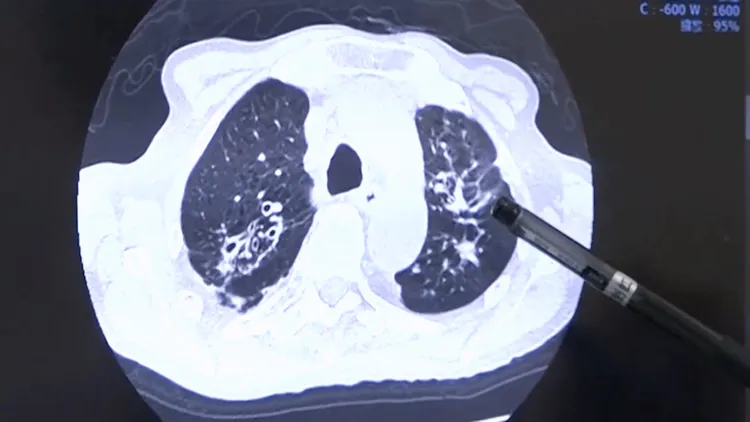

彰化醫院胸腔內科醫師高劍虹指出,陳男2年多前曾經在其他醫院治療肺結核,日前卻又開始咳嗽,特地前往肺結核指定醫院彰化醫院就診,經過X光及痰液化驗,確定肺結核復發,住進隔離病房醫治,進一步做電腦斷層檢查,顯現多處肺結核陰影,乍看之下就是肺結核,但其右中葉的陰影形狀呈尖狀,似乎又不是單純的肺結核。

高劍虹說,根據統計,肺結核病患是罹患肺癌的高危險族群,肺結核團隊覺得這起個案電腦斷層的右胸陰影有肺癌的可能性,因此進行切片,經病理檢驗及正子攝影後確診為初期肺腺癌,交由胸腔外科醫師進行切除,由於是初期,切除後不用再進行化療。

筆端所指即為肺結核陰影。彰化醫院提供